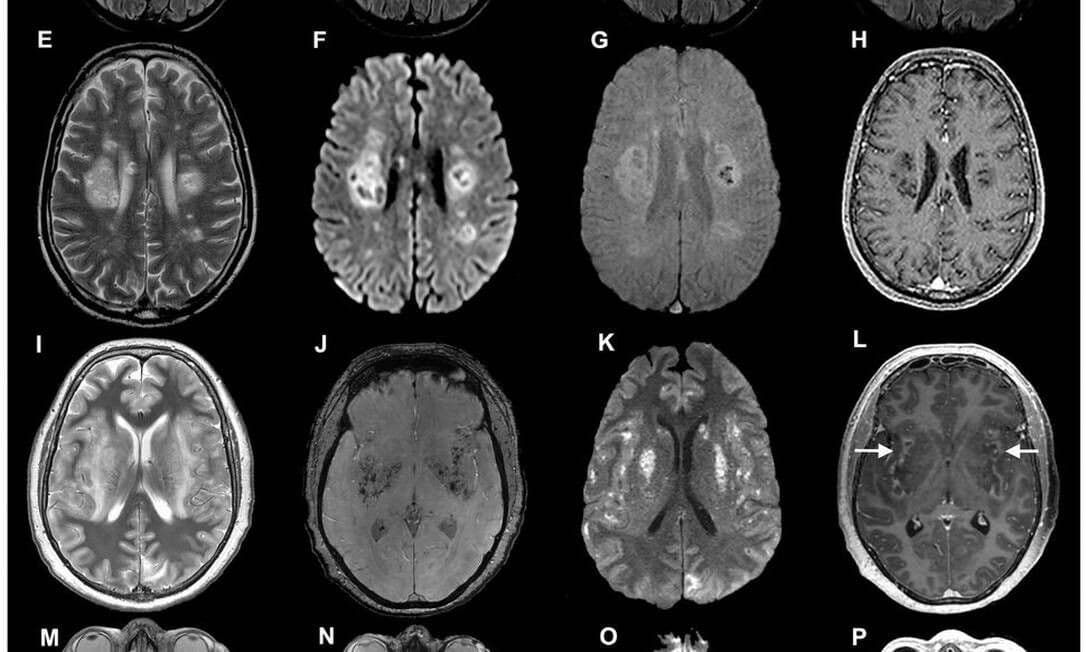

Sars-CoV-2 pode atacar células cerebrais em humanos e camundongos